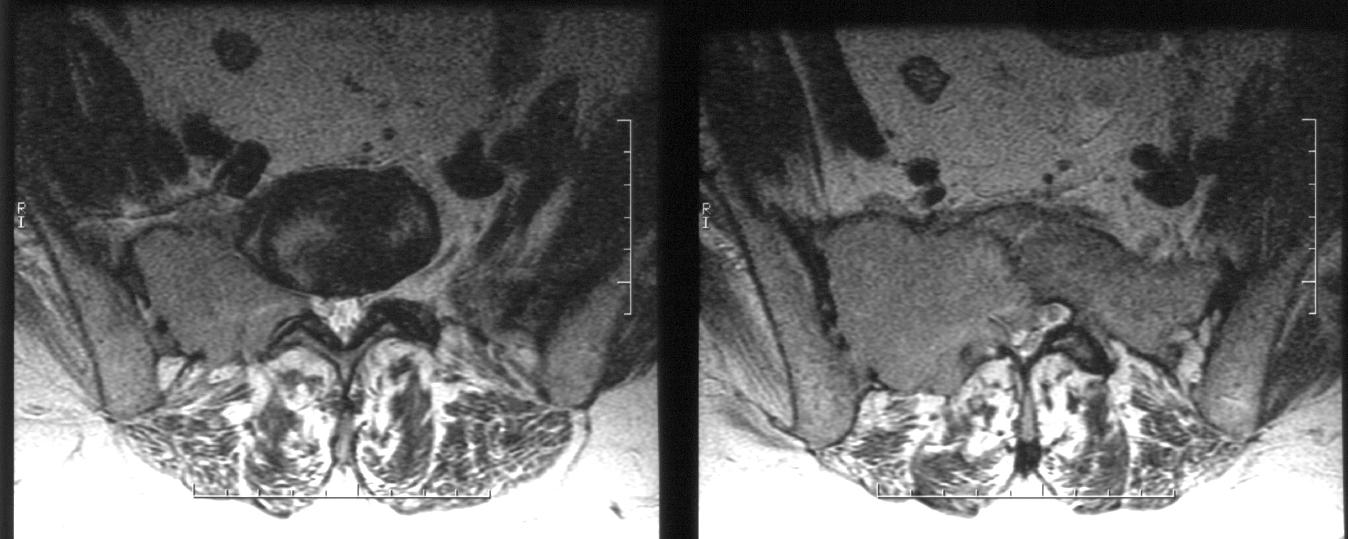

Pe baza acestor investigatii este certificata prezenta unei formatiuni tumorale bine vascularizate la nivel sacrat, cu osteoliza asociata, care se extinde la nivel sacro-iliac drept. Se recomanda completarea investigatiilor cu examinarea RMN cu substanta de contrast a coloanei lombo-sacrate, care confirma descrierea masei osteolitice cu contur neregulat si dimensiuni axiale maxime de 62/63mm la nivelul hemisacrului drept, precum si extensia sacro-iliaca.